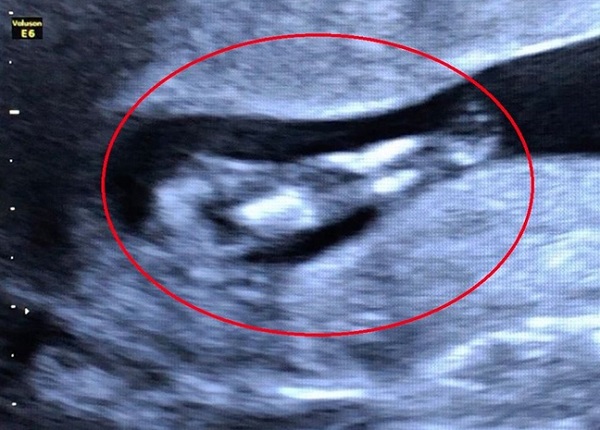

Hình ảnh siêu âm ghi nhận trường hợp thai nhi mắc hội chứng người cá - Ảnh: Bệnh viện Phụ sản Cần Thơ |

Ngày 8/4, bệnh viện Phụ sản Cần Thơ cho biết, các bác sĩ tại khoa Chẩn đoán hình ảnh của bệnh viện vừa phát hiện một trường hợp thai nhi mắc hội chứng người cá (Mermaid Syndrome) rất hiếm gặp với tỉ lệ 1/100.000 trẻ sơ sinh.

Trước đó, thai phụ 32 tuổi đến thăm khám thai định kỳ với tuổi thai 11 tuần 5 ngày. Qua kết quả hình ảnh siêu âm cho thấy thai nhi 2 chân dính vào nhau giống như đuôi cá, bất thường bàng quang và hệ tiết niệu, dây rốn 1 động mạch.

Sau khi phát hiện, các bác sĩ tiếp tục thực hiện các xét nghiệm tầm soát bất thường nhiễm sắc thể, đồng thời tư vấn cho thai phụ về tình trạng dị tật của thai nhi và tiến hành chấm dứt thai kỳ.